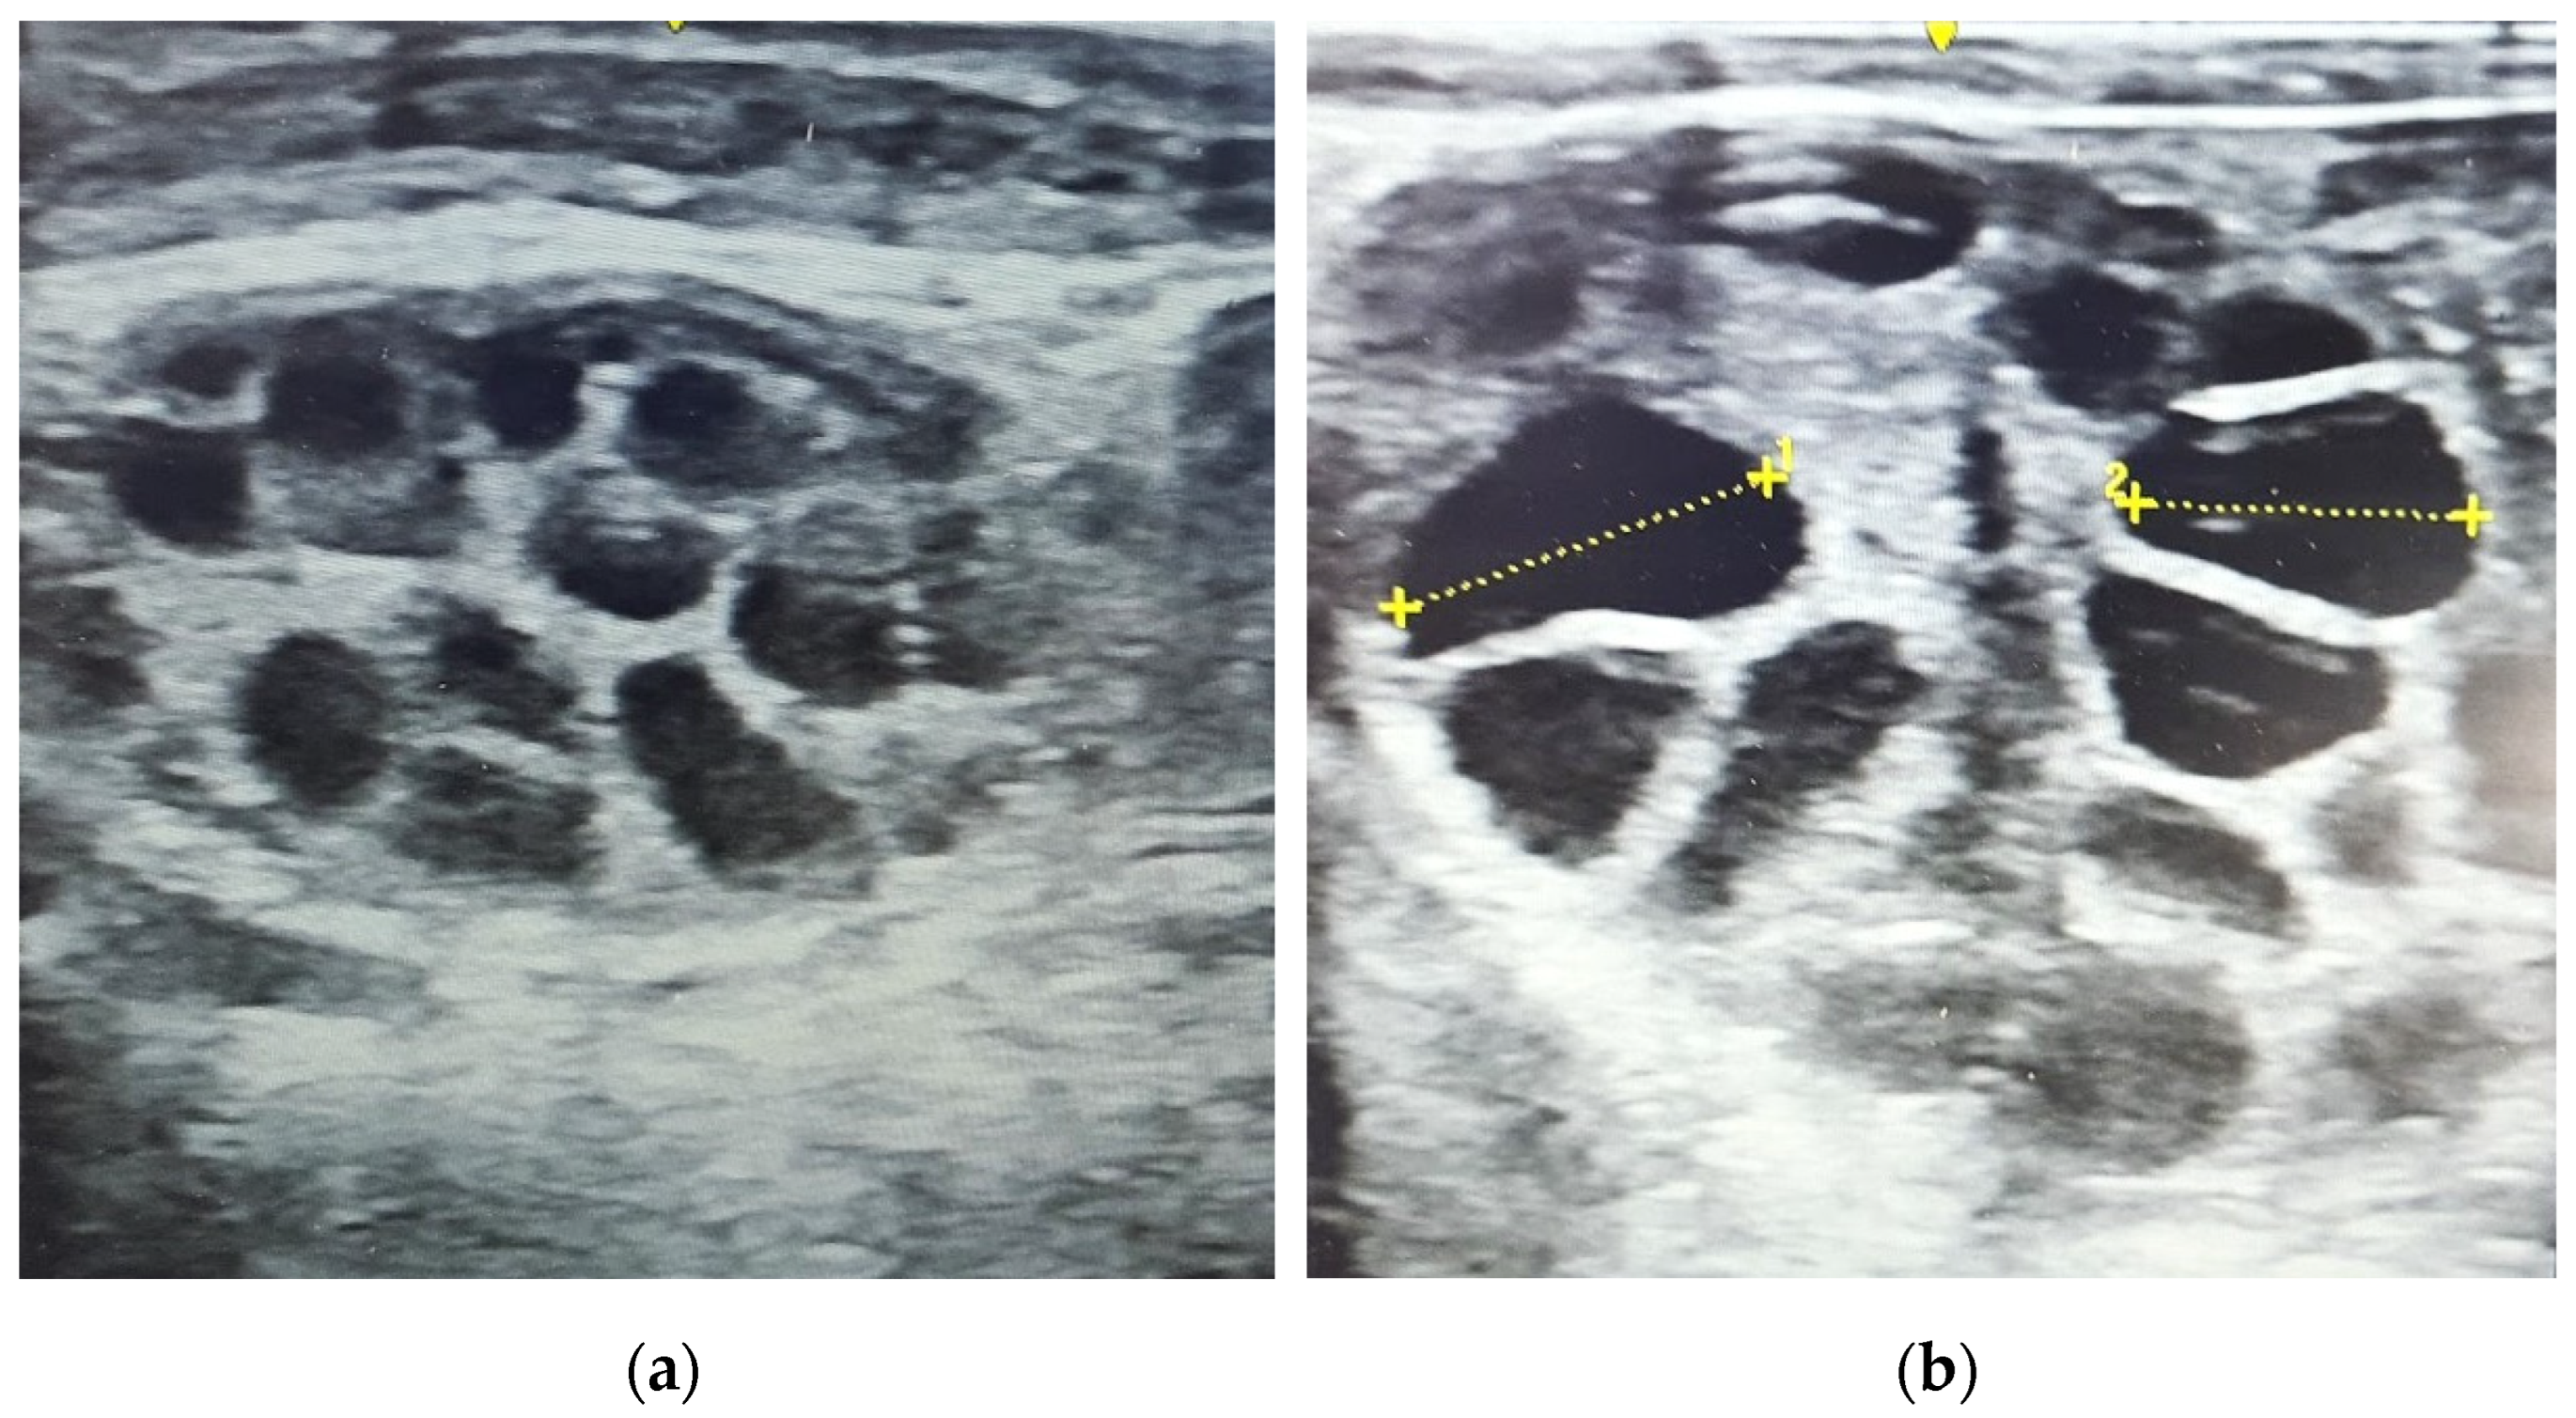

2.5. Embryo Recovery and Assessment of Quality

3.4. Embryo Quantity and Quality